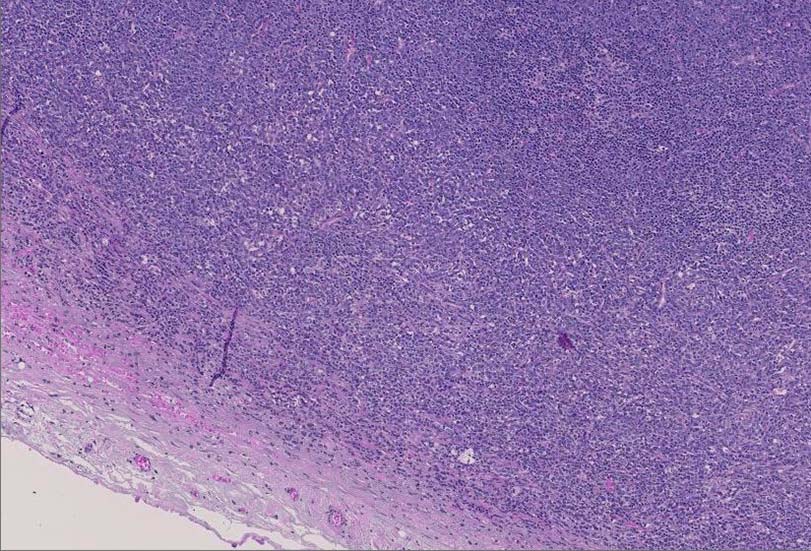

診断に難渋した顆粒球肉腫の1例 静岡赤十字病院 笠原正男: myeloid sarcomaのリンパ節病変.

腫大したリンパ節, 20x17mm. 萎縮した胚中心をもつ濾胞が散在する. 一見, Castleman病様の像. よく見ると, 線維化し軽度に肥厚した被膜下に小リンパ球の乏しい, 低倍で明るくみえる領域を視認できる.(サムネイル画像をクリックで大きな画像がみられます)

拡大像では, 類円形, 卵円形, non-cleaved nucleiをもつN/C比大の大きさのそろった細胞がシート状密に浸潤増殖している.

クロマチンは繊細で核は淡明, 核小体を1から数個もつ.